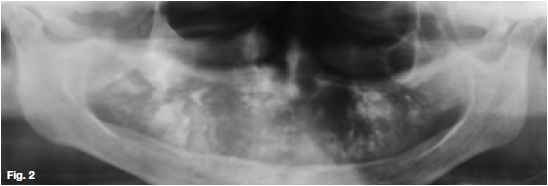

Figures 1, 2, & 3 show a mixed radiolucent/opaque lesion affecting the maxilla, crossing the midline in an edentulous patient, causing flattening of the palate. A lateral skull radiograph of another patient (Fig. 4) shows osteoporosis imperfecta in the posterior and anterior parts of the skull (green arrows) along with thickening of the calvarium and cranial vault which are cardinal radiological signs of the condition. Figures 5 & 6 illustrate "cotton wool" radio-opacities in the skull and the base of the skull shows dense sclerosis. All the images mentioned so far are typical features of Paget's disease. Sir James Paget, surgeon and pathologist who is best remembered for naming Paget's disease. The disease is idiopathic and can be divided into three stages: initial bone resorptive phase, vascular phase with osteoblastic repair, and approximal/ sclerosing phase. The jaws are involved in approximately one in Ave cases, with the maxilla being affected about twice as frequently as the mandible. During the initial phase of bone resorption, the affected bones may be deformed or painful, particularly the weight-bearing structures such as the long bones of the legs (Fig. 7A & B). Later the affected bones expand, commonly in the maxilla, mandible or cranium. At this stage, the dental patient who wears full dentures may complain that the fit of the dentures is becoming progressively poorer. When the maxilla is affected, the alveolar ridge widens and the palatal vault can flatten (Fig. 2). When teeth are present, they may become increasingly spaced, with extensive jaw enlargement. Neurologic complaints can result from increased deposition of bone in the areas of the foramina of the skull causing headaches, auditory disorders progressing to deafness, visual disorders progressing to blindness, facial paresis, and vertigo. The bones are relatively brittle; hence, fractures are likely. Generalised radiolucency/osteoporosis intermediate stage with mixed radiolucency/radiopacity, "driven snow" coarse trabeculation, "cotton wool" radio-opacities in the final stage (Figs. 5 & 6). Hypercementosis, loss of lamina dura, obliteration of the periodontal ligament spaces (Fig. 8) and external root resorption (Fig. 9) may also be present. The upper hand wrist radiograph (Fig.10) of another patient shows the disease affecting the phalanx of the third digit.